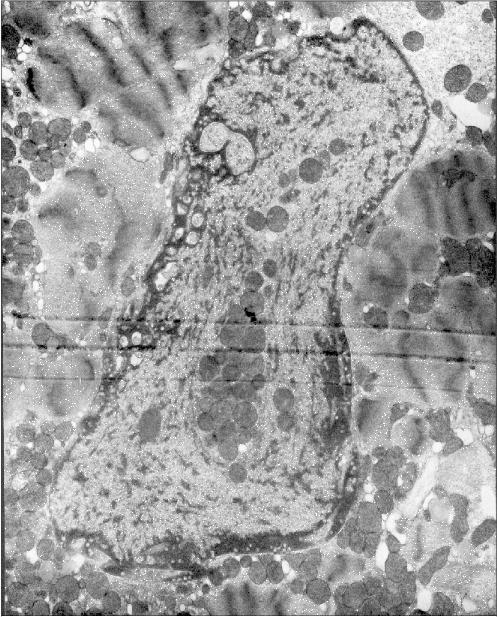

Figure 1 presents three patients' cardiomyocyte nuclei that contain mitochondrial clusters. Two patients were with hypertrophic cardiomyopathy and the third patient had alcoholic cardiomyopathy. One can see that the mitochondria are not separated by the nuclear membrane from the nuclear contents. This means that mitochondria are present in the nucleoplasm and not in a nuclear envelop invagination. All three microphotographs show the continuity of the nuclear membrane that separates the nuclear interior (with the mitochondria) from the cytosol.

Figure 1b

Fig. 1b. Intranuclear location of mitochondria in cardiomyocytes of patients with heart failure: patient Sh. (hypertrophic cardiomyopathy); ×52,300.

Examination of microphotographs of the mitochondria-containing nuclei shows that in most cases we are dealing with the cells that are entering apoptosis. Thus, most of the figures in the present article show chromatin margination (the accumulation at the edges of the nucleus) that is typical for apoptosis.